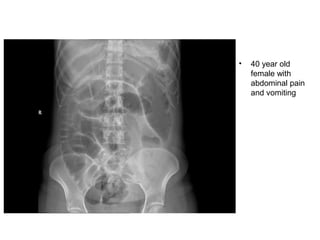

• 40 year old

female with

abdominal pain

and vomiting

• 40 yearold female with abdominal pain and vomiting